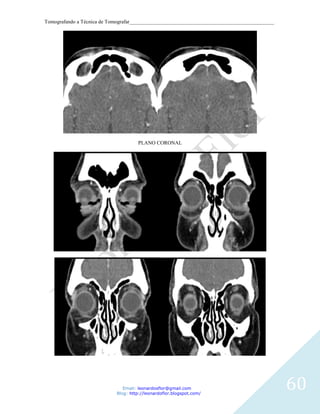

PLANO CORONAL